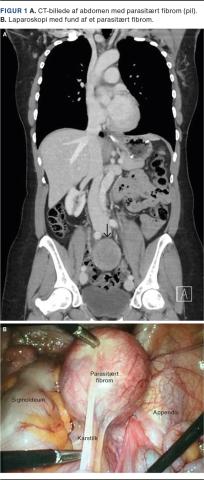

Otte år senere blev hun indlagt akut i gastrokirurgisk regi pga. diffuse smerter i nedre abdomen. Ved CT fandt man en proces på 5 × 7 cm foran os sacrum med formodet udgangspunkt i højre ovarium (Figur 1A). Hun blev derfor henvist til en gynækologisk afdeling, hvor man ved UL-skanning fandt et normalt højre ovarium, men fik fornemmelse af en vaskulariseret stilk fra højre ovarium til en 5 × 4,7 × 5,5 cm stor fibromlignende proces. Venstre ovarium så naturligt ud. Cancerantigen-125 blev målt til 19 kE/l (normalværdi: < 35 kE/l). Smerterne gik i ro, og hun blev udskrevet til ambulant kontrol tre uger senere, hvor hun fortsat var generet af mavesmerter og oppustethed. Der blev foretaget MR-skanning af genitalia interna, hvor man genfandt en solid velafgrænset struktur på 5 × 7 cm beliggende i højre side af det lille bækken adskilt fra ovarier og kar. Hun blev tilbudt laparoskopisk fjernelse, hvor man fandt normale ovarier, men en fibromlignende struktur på 5 × 5 cm med karforsyning fra området omkring coecum (Figur 1B). Der var ingen relation til højre ovarium, og de øvrige abdominalorganer var normale. Fibromet blev in toto fjernet i pose gennem en udvidet incision i venstre fossa iliaca. Operationen forløb ukompliceret, og hun var efterfølgende symptomfri. Histologisk undersøgelse viste leiomyom uden tegn til malignitet.